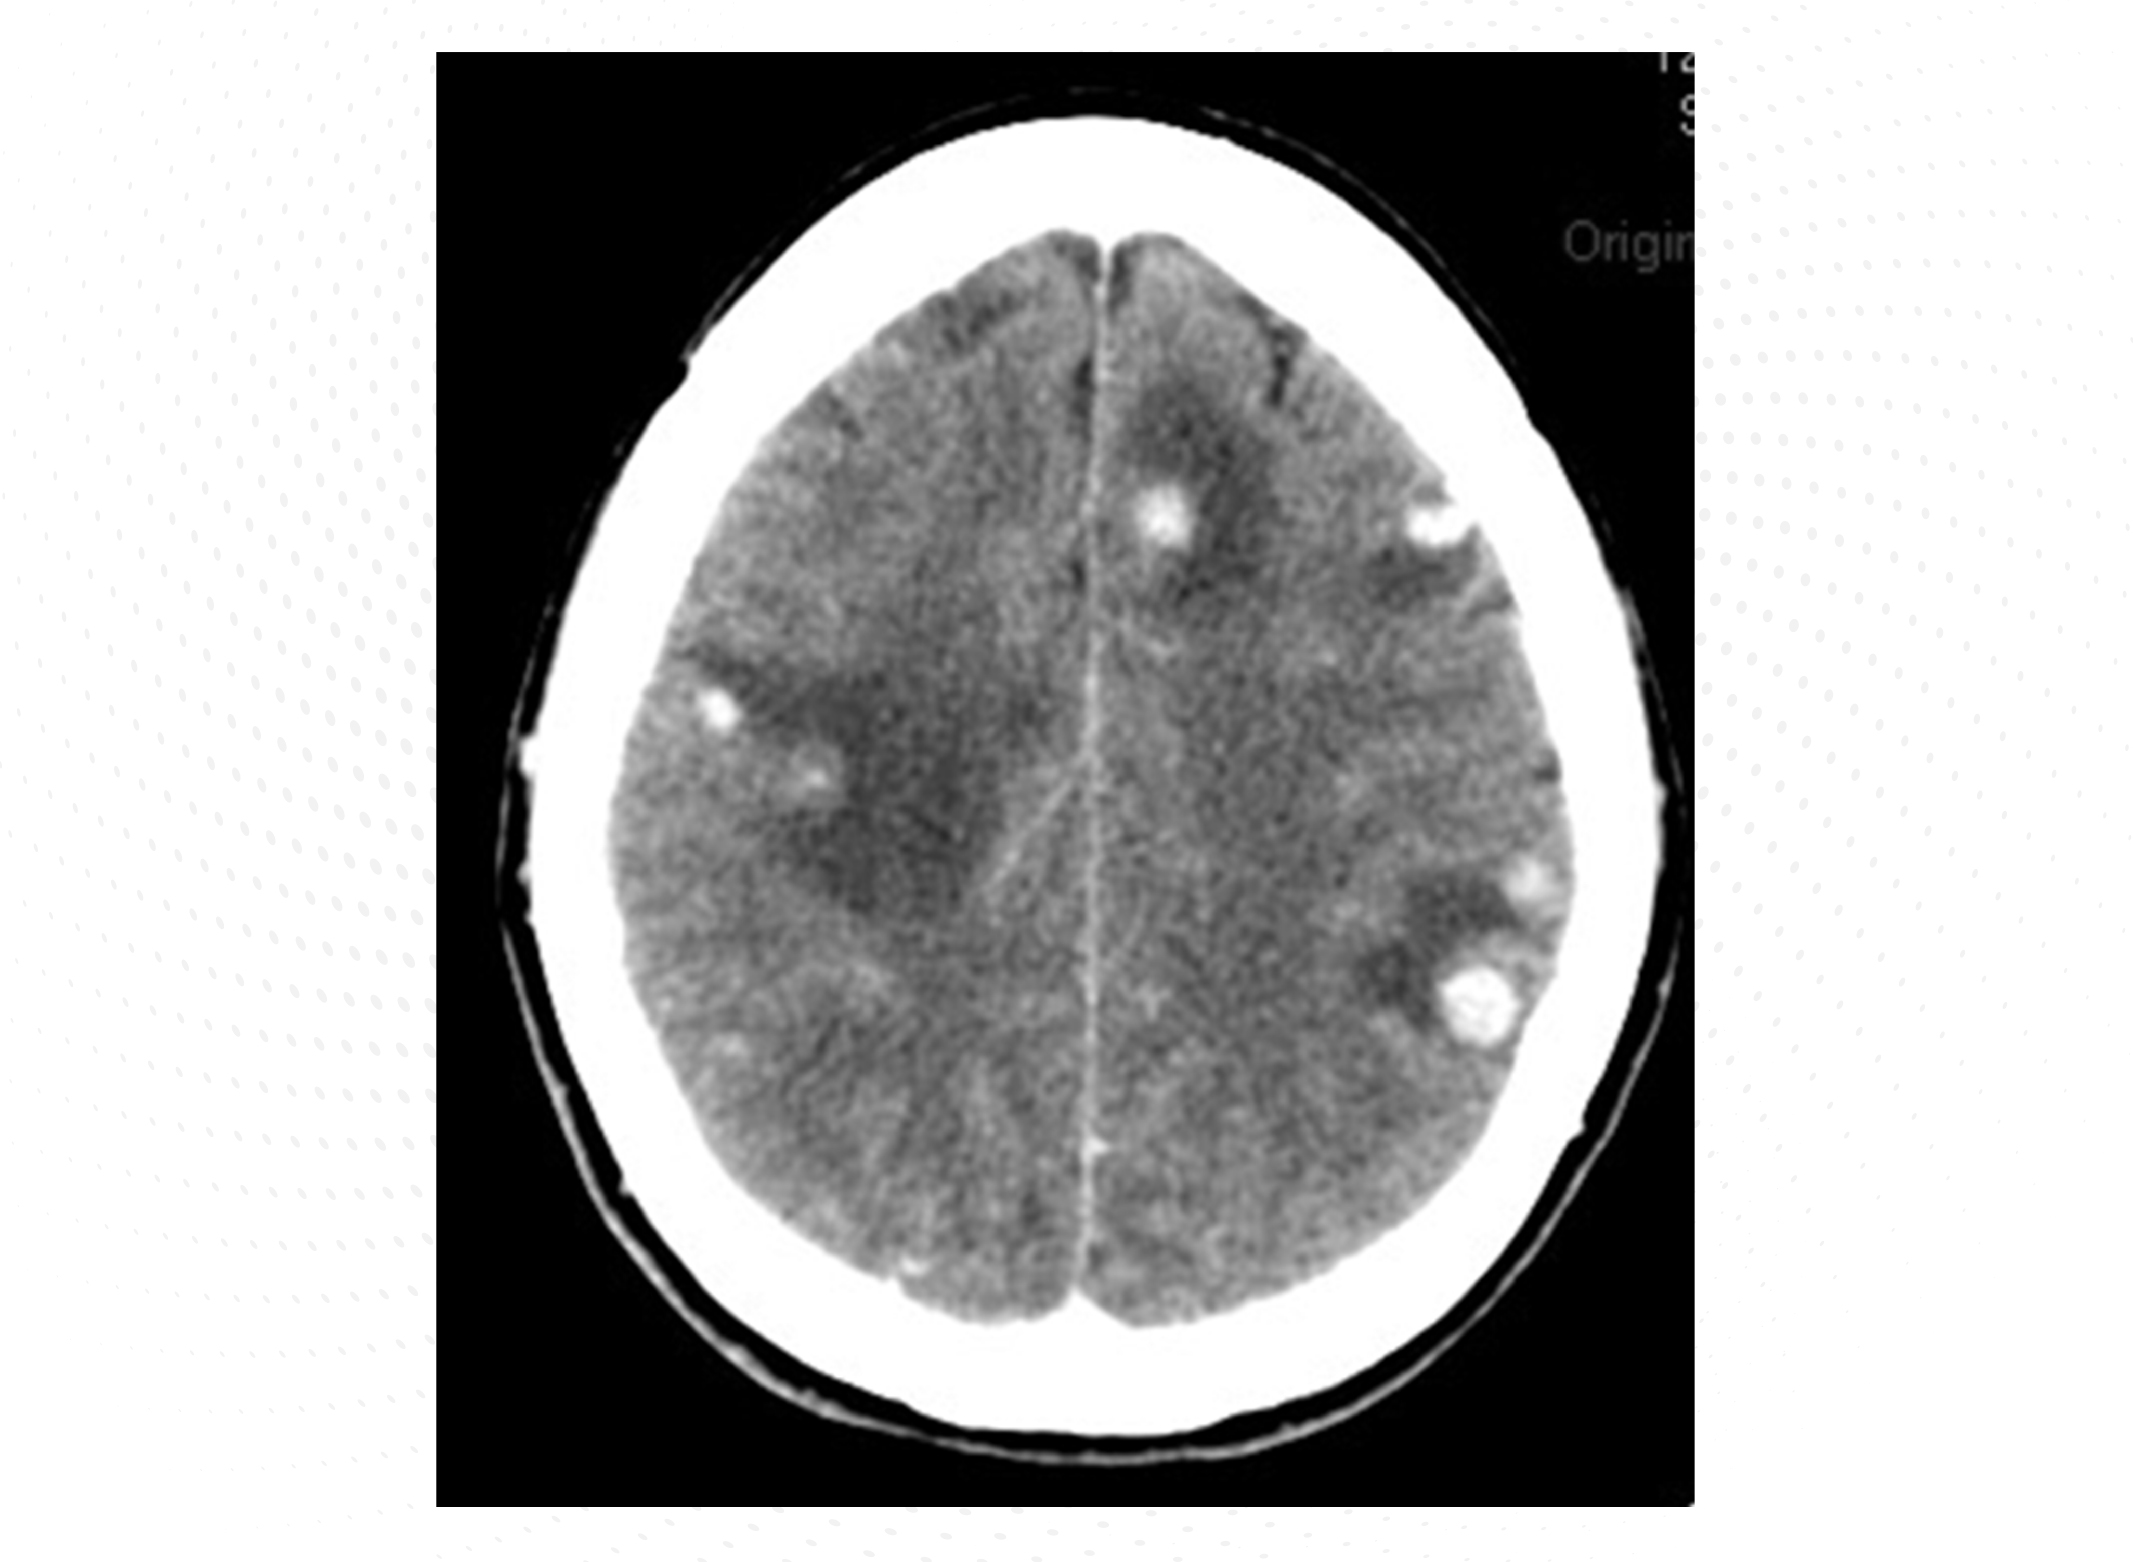

Se trata de una mujer de 56 años sin antecedentes de interés, diagnosticada recientemente de cáncer de mama ductal infiltrante localmente avanzado con metástasis hepáticas y linfangitis pulmonar e insuficiencia respiratoria secundaria. La paciente comenzó el primer ciclo de quimioterapia con paclitaxel y 3 meses después se le añadió trastuzumab en el segundo ciclo de quimioterapia. Una semana después de comenzar dicho ciclo, consulta con molestias, ligero empastamiento del miembro inferior izquierdo, por lo que se le realizó una ecografía compresiva de miembros inferiores, encontrando un déficit de compresibilidad en la vena poplítea izquierda (Figura 1). Con el diagnóstico de trombosis venosa profunda (TVP) de la vena poplítea izquierda, se realizó analítica urgente que evidenció un aclaramiento de creatinina de 79 mL/min, con cifras de plaquetas y hemoglobina dentro de rango de la normalidad. Se inició tratamiento con bemiparina 7.500 UI/24 horas (peso: 62 kg).